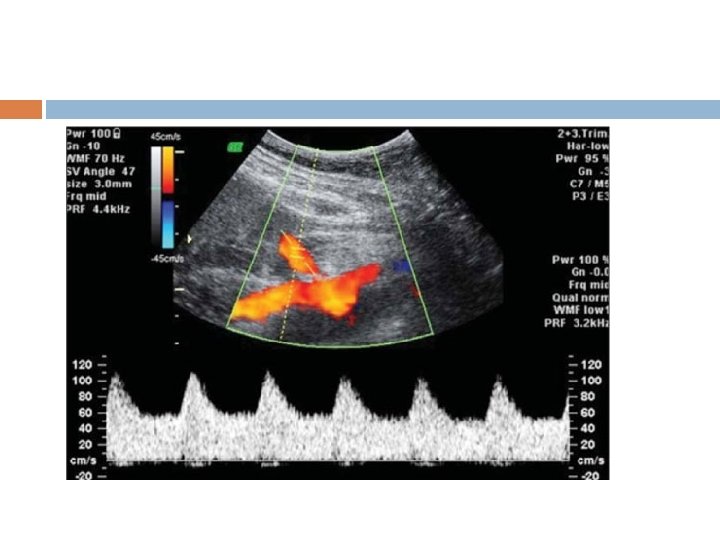

Ductus Venosus

Protocol for the assessment of the ductus venosus The gestational period must be 11 to 13 weeks and six days. The examination should be undertaken during fetal quiescence. The magnification of the image fetal thorax and abdomen occupy the whole image. A right ventral mid-sagittal view of the fetal trunk should be obtained and color flow mapping should be undertaken to demonstrate the umbilical vein, ductus venosus and fetal heart. The pulsed Doppler sample volume should be small (0. 5 -1. 0 mm) The insonation angle less than 30 degrees. The filter should be set at a low frequency (50 -70 Hz) The sweep speed should be high (2 -3 cm/s) so that the waveforms are spread allowing better assessment of the a-wave.

Interpretation of Ductus Venosus Normal a wave Combined Test <1: 50 >1: 50 Anomaly Invasive testing reversal of a wave Combined Test <1: 50 Other Markers >1: 50 Invasive testing Anomaly & fetal Echo

DUCTUS VENOSUS FLOW NO OF CASES ANOMALIES 942 REVERSAL 18 ANEUPLOIDIES CARDIAC 4 9